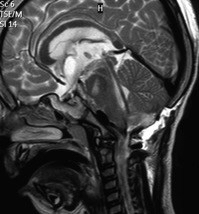

le plus souvent, la tumeur se révèle par une hydrocéphalie, liée à l’obstruction du V4 ; par une ataxie, liée à l’atteinte du pédoncule cérébelleux ; l’anorexie est un mode de révélation surtout chez le petit nourrisson, réalisant un syndrome de Russell

qui doit être prudente en raison de l’infiltration du plancher du V4 : il existe un risque de paralysie faciale (ci-contre), de mutisme, de troubles oculomoteurs, d’ataxie.